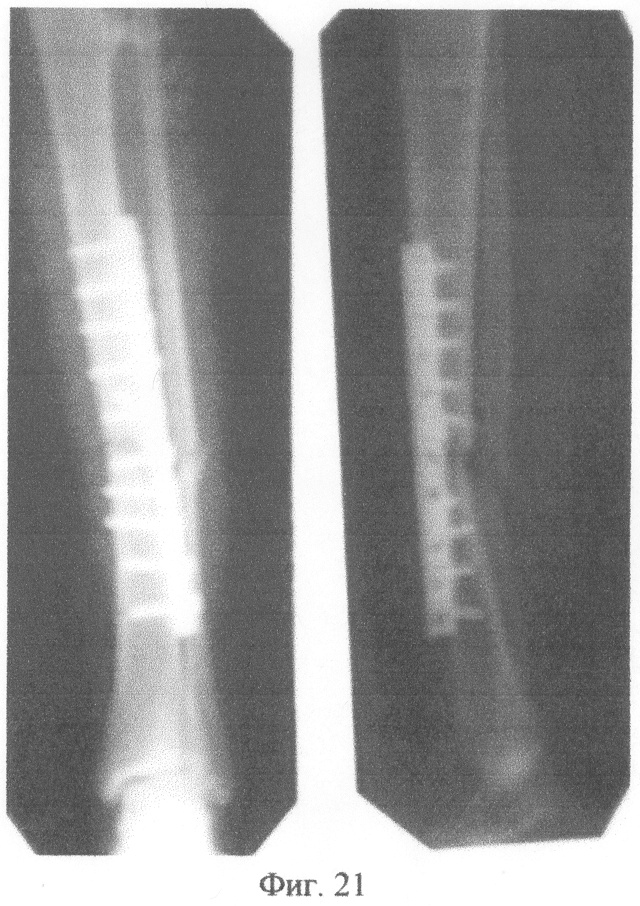

Сделана рентгенограмма левой голени в двух проекциях до операции (фиг.21). После обследования и предоперационной подготовки произведены операции.

2. Блокирующий интрамедуллярный остеосинтез отломков большеберцовой кости левой голени.

Под интубационным наркозом удалена пластина из большеберцовой кости. Имелась подвижность отломков в области перелома, проведена репозиция и фиксация отломков большеберцовой кости внутрикостным канюлированным стержнем с блокирующими винтами. Дистальное блокирование канюлированного стержня осуществлено предлагаемым способом. В костно-мозговой канал большеберцовой кости введена направляющая спица. По отметке на шкале направляющей спицы определена длина канюлированного стержня (320 мм). Произведена подготовка дистального целенаправителя: приведены в соответствие отверстия в блоке дистального целенаправителя отверстиям на рабочем конце канюлированного стержня. Введен в костномозговой канал большеберцовой кости подготовленный канюлированный стержень длиной 320 мм. Держателем выдвинута направляющая спица. Через нижнее отверстие в блоке подготовленного дистального целенаправителя сверлом сформирован канал в кости, проходящий через ниже расположенное отверстие рабочего конца канюлированного стержня. Контроль прохождения сверла через ниже расположенное отверстие на рабочем конце канюлированного стержня осуществлен следующим образом: держателем направляющая спица проведена в дистальном направлении по каналу стержня, она встретила сопротивление на уровне ниже расположенного отверстия на рабочем конце канюлированного стержня; по отметке на шкале направляющей спицы показатель равен 320 мм, что соответствует разнице между длиной канюлированного стержня (340 мм) и расстоянием от рабочего конца канюлированного стержня до ниже расположенного отверстия на рабочем конце канюлированного стержня (20 мм). Просверлен второй кортикальный слой кости, удалено сверло. Через нижнее отверстие в блоке дистального целенаправителя введен в сформированный канал блокирующий винт. Контроль прохождения блокирующего винта через ниже расположенное отверстие на рабочем конце канюлированного стержня осуществлен следующим образом: держателем направляющая спица проведена в дистальном направлении по каналу стержня, она встретила сопротивление блокирующего винта на уровне ниже расположенного отверстия на рабочем конце канюлированного стержня; по отметке на шкале направляющей спицы показатель равен 320 мм, что соответствует разнице между длиной канюлированного стержня (340 мм) и расстоянием от рабочего конца канюлированного стержня до уровня ниже расположенного отверстия на рабочем конце канюлированного стержня (20 мм).

Через верхнее отверстие в блоке дистального целенаправителя сверлом сформировали канал в кости, проходящий через выше расположенное отверстие на рабочем конце канюлированного стержня. Контроль прохождения сверла через выше расположенное отверстие на рабочем конце канюлированного стержня осуществлен следующим образом: держателем направляющая спица проведена в дистальном направлении по каналу стержня, она встретила сопротивление сверла на уровне выше расположенного отверстия на рабочем конце канюлированного стержня; по отметке на шкале направляющей спицы показатель равен 295 мм, что соответствует разнице между длиной канюлированного стержня (240 мм) и расстоянием от рабочего конца канюлированного стержня до уровня выше расположенного отверстия на рабочем конце канюлированного стержня (45 мм). Просверлен второй кортикальный слой кости, удалено сверло.

Через верхнее отверстие в блоке дистального целенаправителя введен в сформированный канал блокирующий винт. Контроль прохождения блокирующего винта через выше расположенное отверстие на рабочем конце канюлированного стержня осуществлен следующим образом: держателем направляющая спица проведена в дистальном направлении по каналу стержня, она встретила сопротивление блокирующего винта на уровне выше расположенного отверстия на рабочем конце канюлированного стержня; по отметке на шкале направляющей спицы показатель равен 295 мм, что соответствует разнице между длиной канюлированного стержня (240 мм) и расстоянием от рабочего конца канюлированного стержня до уровня выше расположенного отверстия на рабочем конце канюлированного стержня (45 мм). Произведено проксимальное блокирование канюлированного стержня. Сделана контрольная рентгенограмма в двух проекциях передвижным рентгенаппаратом (фиг.22). Продолжительность операции 50 минут.